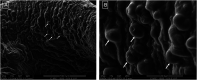

Encapsulation of biological components in hydrogels is a well described method for controlled drug delivery of proteins, tissue engineering and intestinal colonization with beneficial bacteria. Given the potential of tissue engineering in clinical practice, this study aimed to evaluate the feasibility of encapsulation of adipose tissue-derived mesenchymal stem cells (MSCs) of mules in sodium alginate. We evaluated capsule morphology and cell viability, immunophenotype and release after encapsulation. Circular and irregular pores were observed on the hydrogel surface, in which MSCs were present and alive. Capsules demonstrated good capacity of absorption of liquid and cell viability was consistently high through the time points, indicating proper nutrient diffusion. Flow cytometry showed stability of stem cell surface markers, whereas immunohistochemistry revealed the expression of CD44 and absence of MHC-II through 7 days of culture. Stem cell encapsulation in sodium alginate hydrogel is a feasible technique that does not compromise cell viability and preserves their undifferentiated status, becoming a relevant option to further studies of tridimensional culture systems and in vivo bioactive agents delivery.